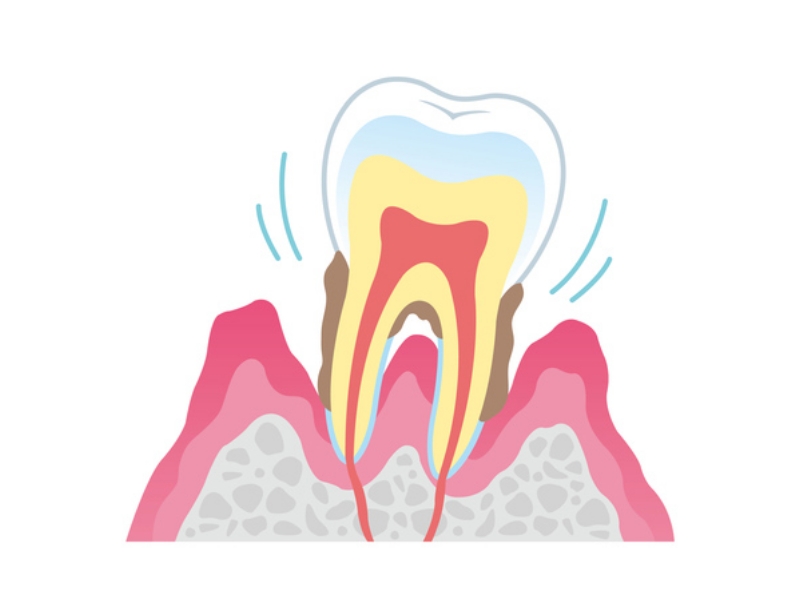

歯周病の進行度

第三段階中等度歯周炎

中等度の歯周炎では、歯周ポケットがさらに深くなり、歯槽骨の吸収が進行します。歯のグラつきや口臭など、症状が徐々に現れ始めます。治療には、スケーリング・ルートプレーニングが必要です。歯周外科処置が必要になることもあります。

-

第四段階重度歯周炎

重度の歯周炎では、歯槽骨の大部分が失われ、歯を支える機能が著しく低下します。歯のグラつきが顕著になり、歯肉から膿が出てくるケースもあります。この段階では、歯を保存することが困難です。抜歯を検討し、抜歯後は、欠損部の機能回復のために、インプラントや義歯などの補綴治療が必要になります。